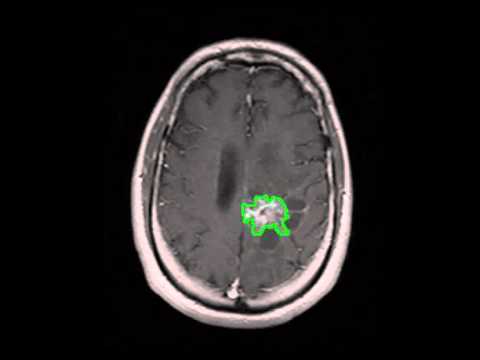

Brain Tumor Detection

Images of Brain Tumor Detection

Brain Tumor Detection Pictures

Malignant Brain Tumor Detection - IJCTE

Abstract—Brain tumor, a mass of tissue that grows out of control is one of the major causes for the increase in mortality among children and adults. ... Fetch Document